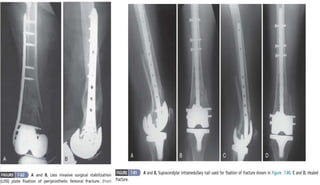

PERIPROSTHETIC FRACTURES

 Supracondylar fracture: 0.3% to 2%

◦ Fixation: ORIF with blade plates, condylar screw plates,

buttress plates + grafts / Rush pins under fluoroscopic

guidance / locked supracondylar IM nail.

 Tibial fractures

◦ # with loose implant: revision,

bone grafting, stemmed

implants.

◦ Stable implant + Undisplaced #:

Non-operative

◦ Stable implant + Displaced #:

ORIF